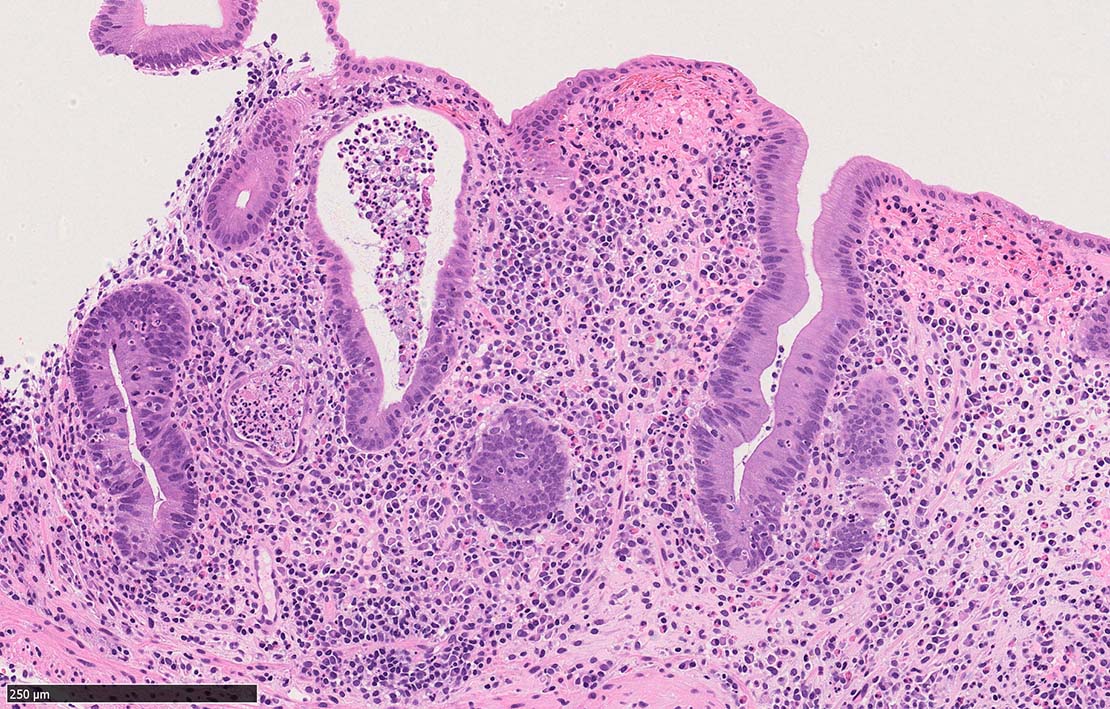

びらんを示す結腸粘膜. 陰窩はdeletion, 萎縮, distortionを呈する. 粘膜固有層には密な慢性炎症がみられ, 好酸球浸潤も多い.粘膜筋板へも炎症細胞浸潤が及ぶ.

UCのような, crypt abscess, cryptitisが認められる. 特徴的な所見として, apoptosis bodiesの増加が見られる.